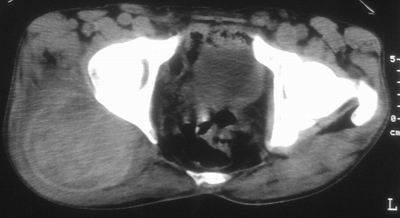

标题: CT16837:M63Y,右臀部巨大软组织包块 [打印本页]

标题: CT16837:M63Y,右臀部巨大软组织包块

患者,男,63岁,自诉3个月前发现右臀部包块,触及疼痛,治疗后缩小。前天突然增大。无高热病史。

考虑-----右臀大肌,臀中肌---感染性病变可能性大。

病灶内部可见出血,首先考虑急性出血性病变.血肿?

给个骨窗,判断一下肿块是否与髂骨有关,肿块内出血是肯定的,至于是感染形成的脓肿还是起源于肌肉或纤维组织的肉瘤则难以确定,不过从影像上看,包膜完整,且环形增厚,病灶下部见斑片状底密度坏死,个人倾向感染可能性大

肌间隙明显混浊,三个月前治疗有缩小,支持考虑臀大肌下脓肿伴出血,肿瘤如果出现瘤内出血的话瘤外边界应该较清楚,现在表现为一种恶性征像,但骨质无明显异常,且臀小肌边界清楚,不符合恶性表现.